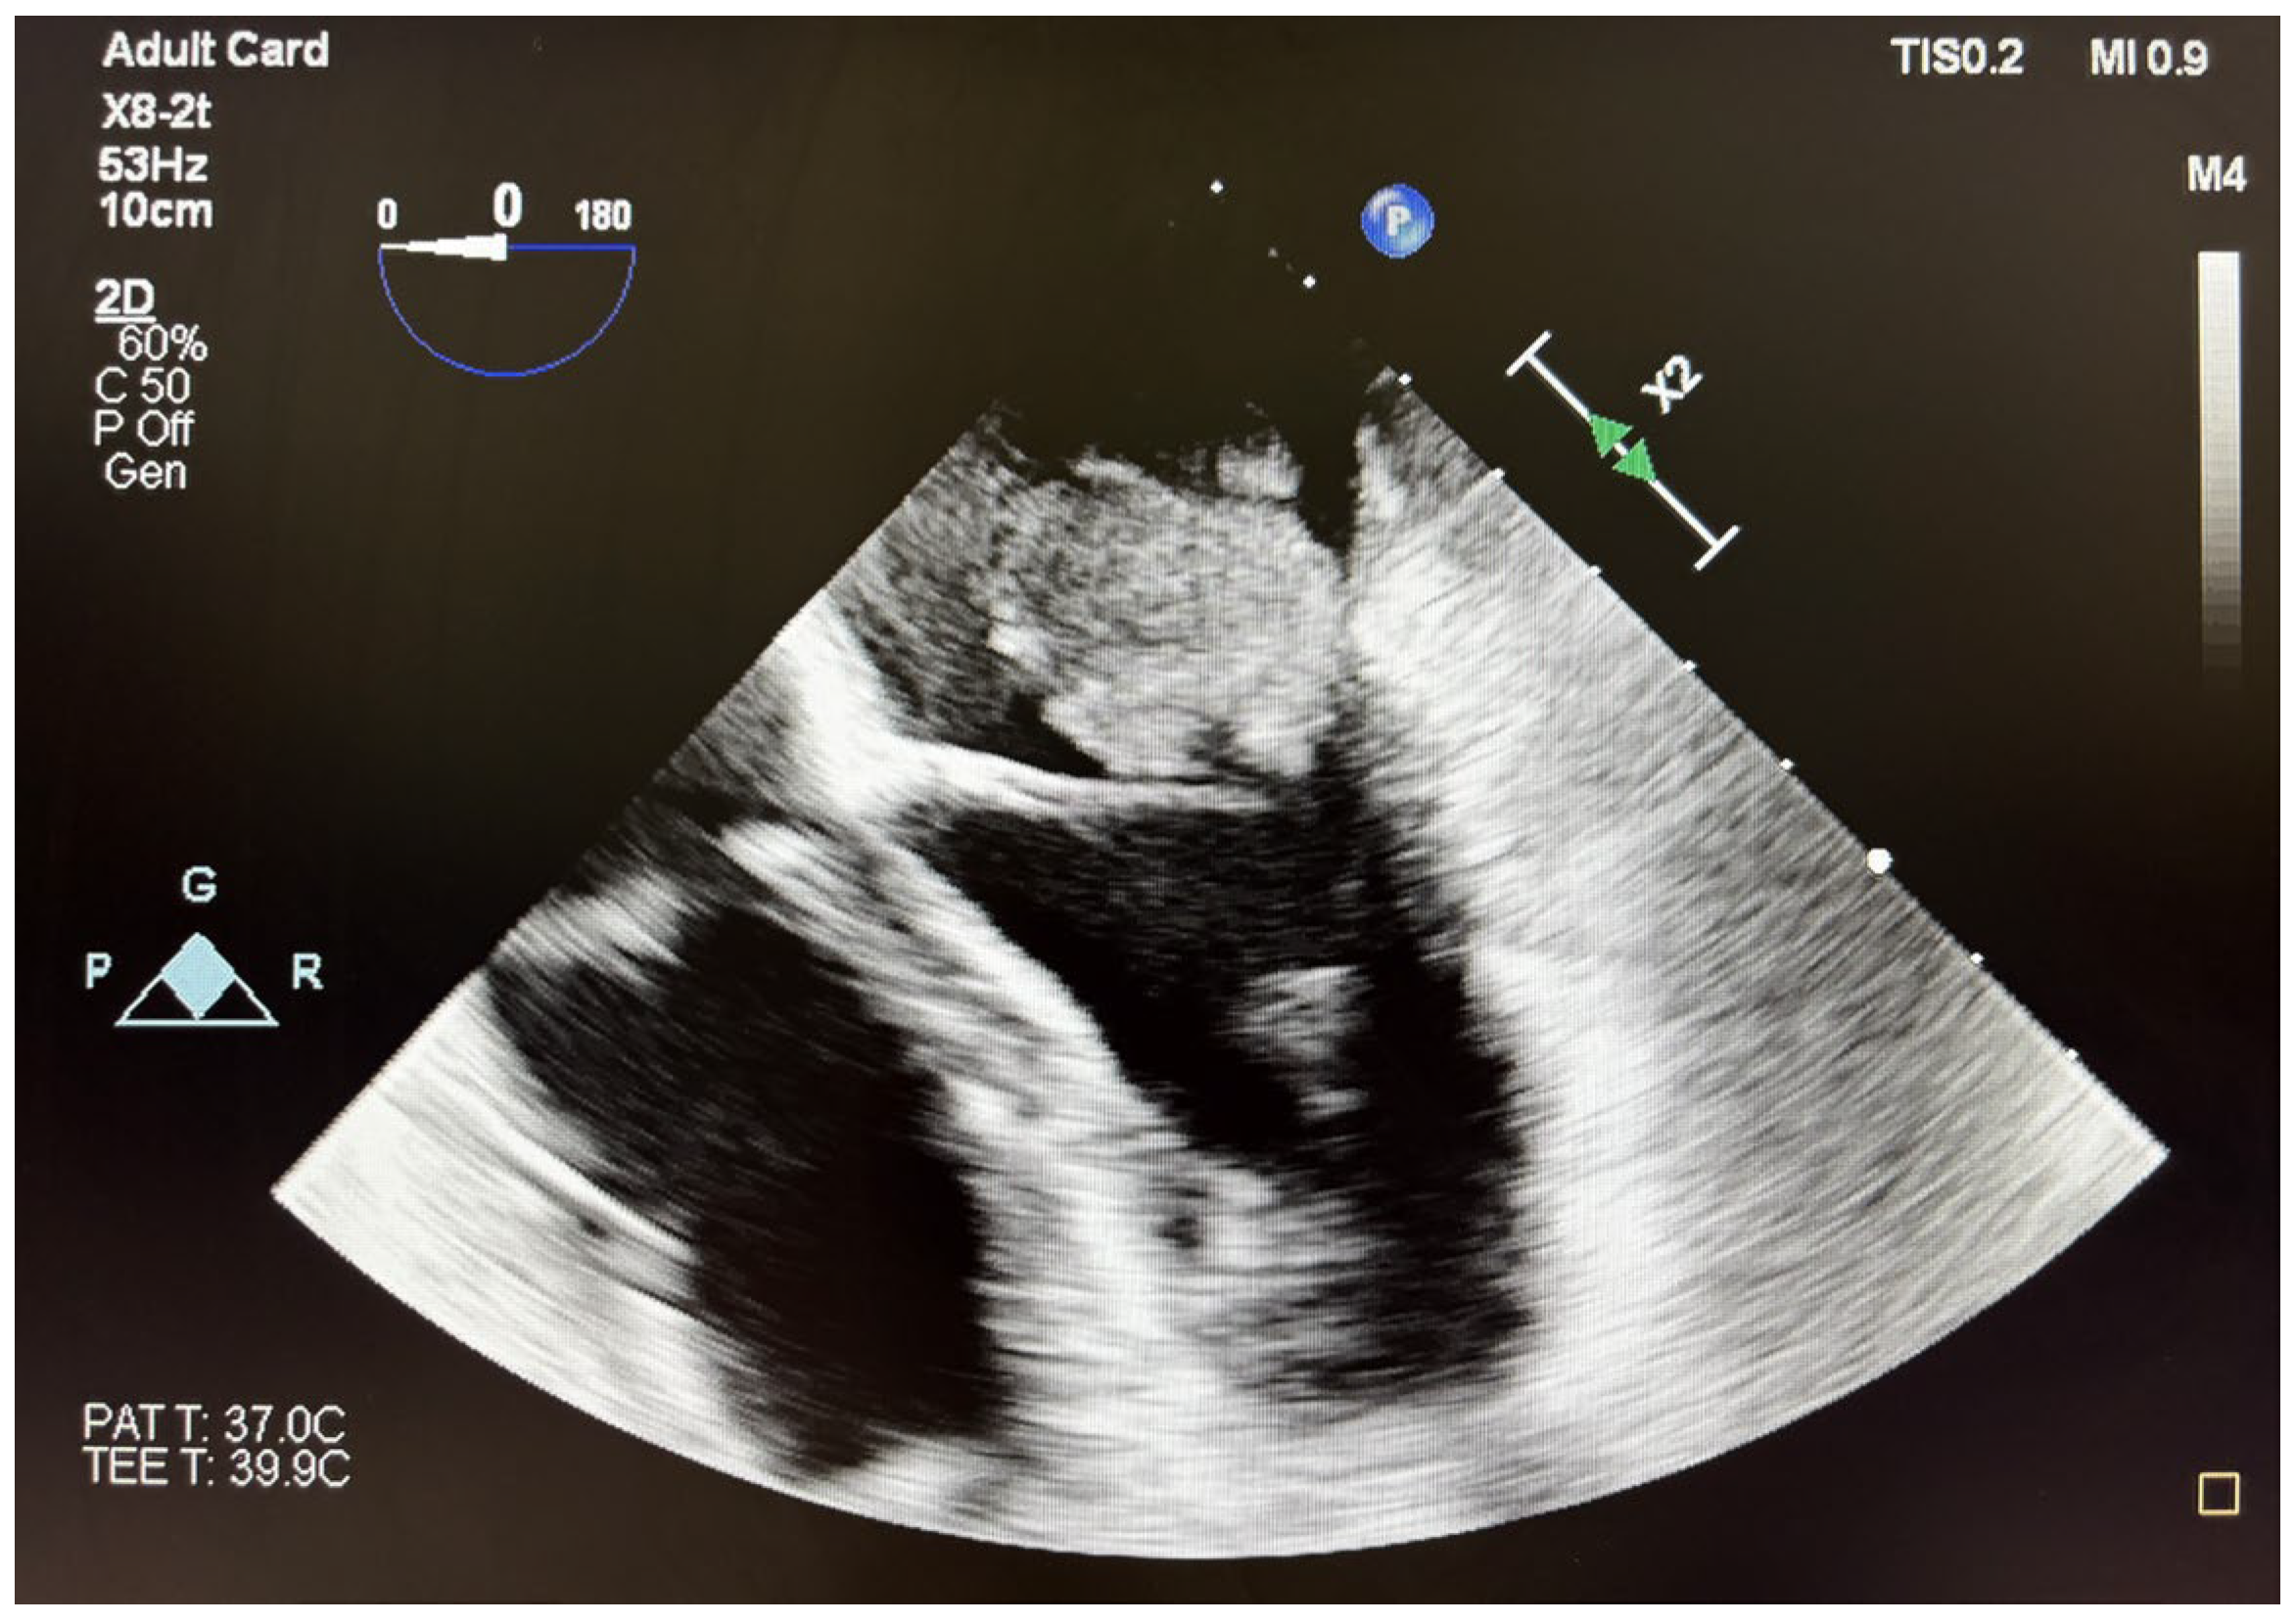

A transesophageal echocardiography to characterize the formation attached to the mitral valve revealed a tumor attached to the poster leaflet at the level of P1/P2 with the longest dimension of 2.8 × 3 cm (7 cm2 area) causing severe mitral stenosis and mild regurgitation (Figure 2). These results were highly suggestive of a myxoma, with increased risk of embolism. An additional formation attached to the postero-medial papillary muscle with similar echogenicity was also observed, as opposed to the usual presentation of the myxomas.

Figure 2. Preoperative TEE images of the intracardiac mass with a maximum diameter of 3 cm, attached to the P2/P3 scallop of the mitral valve.